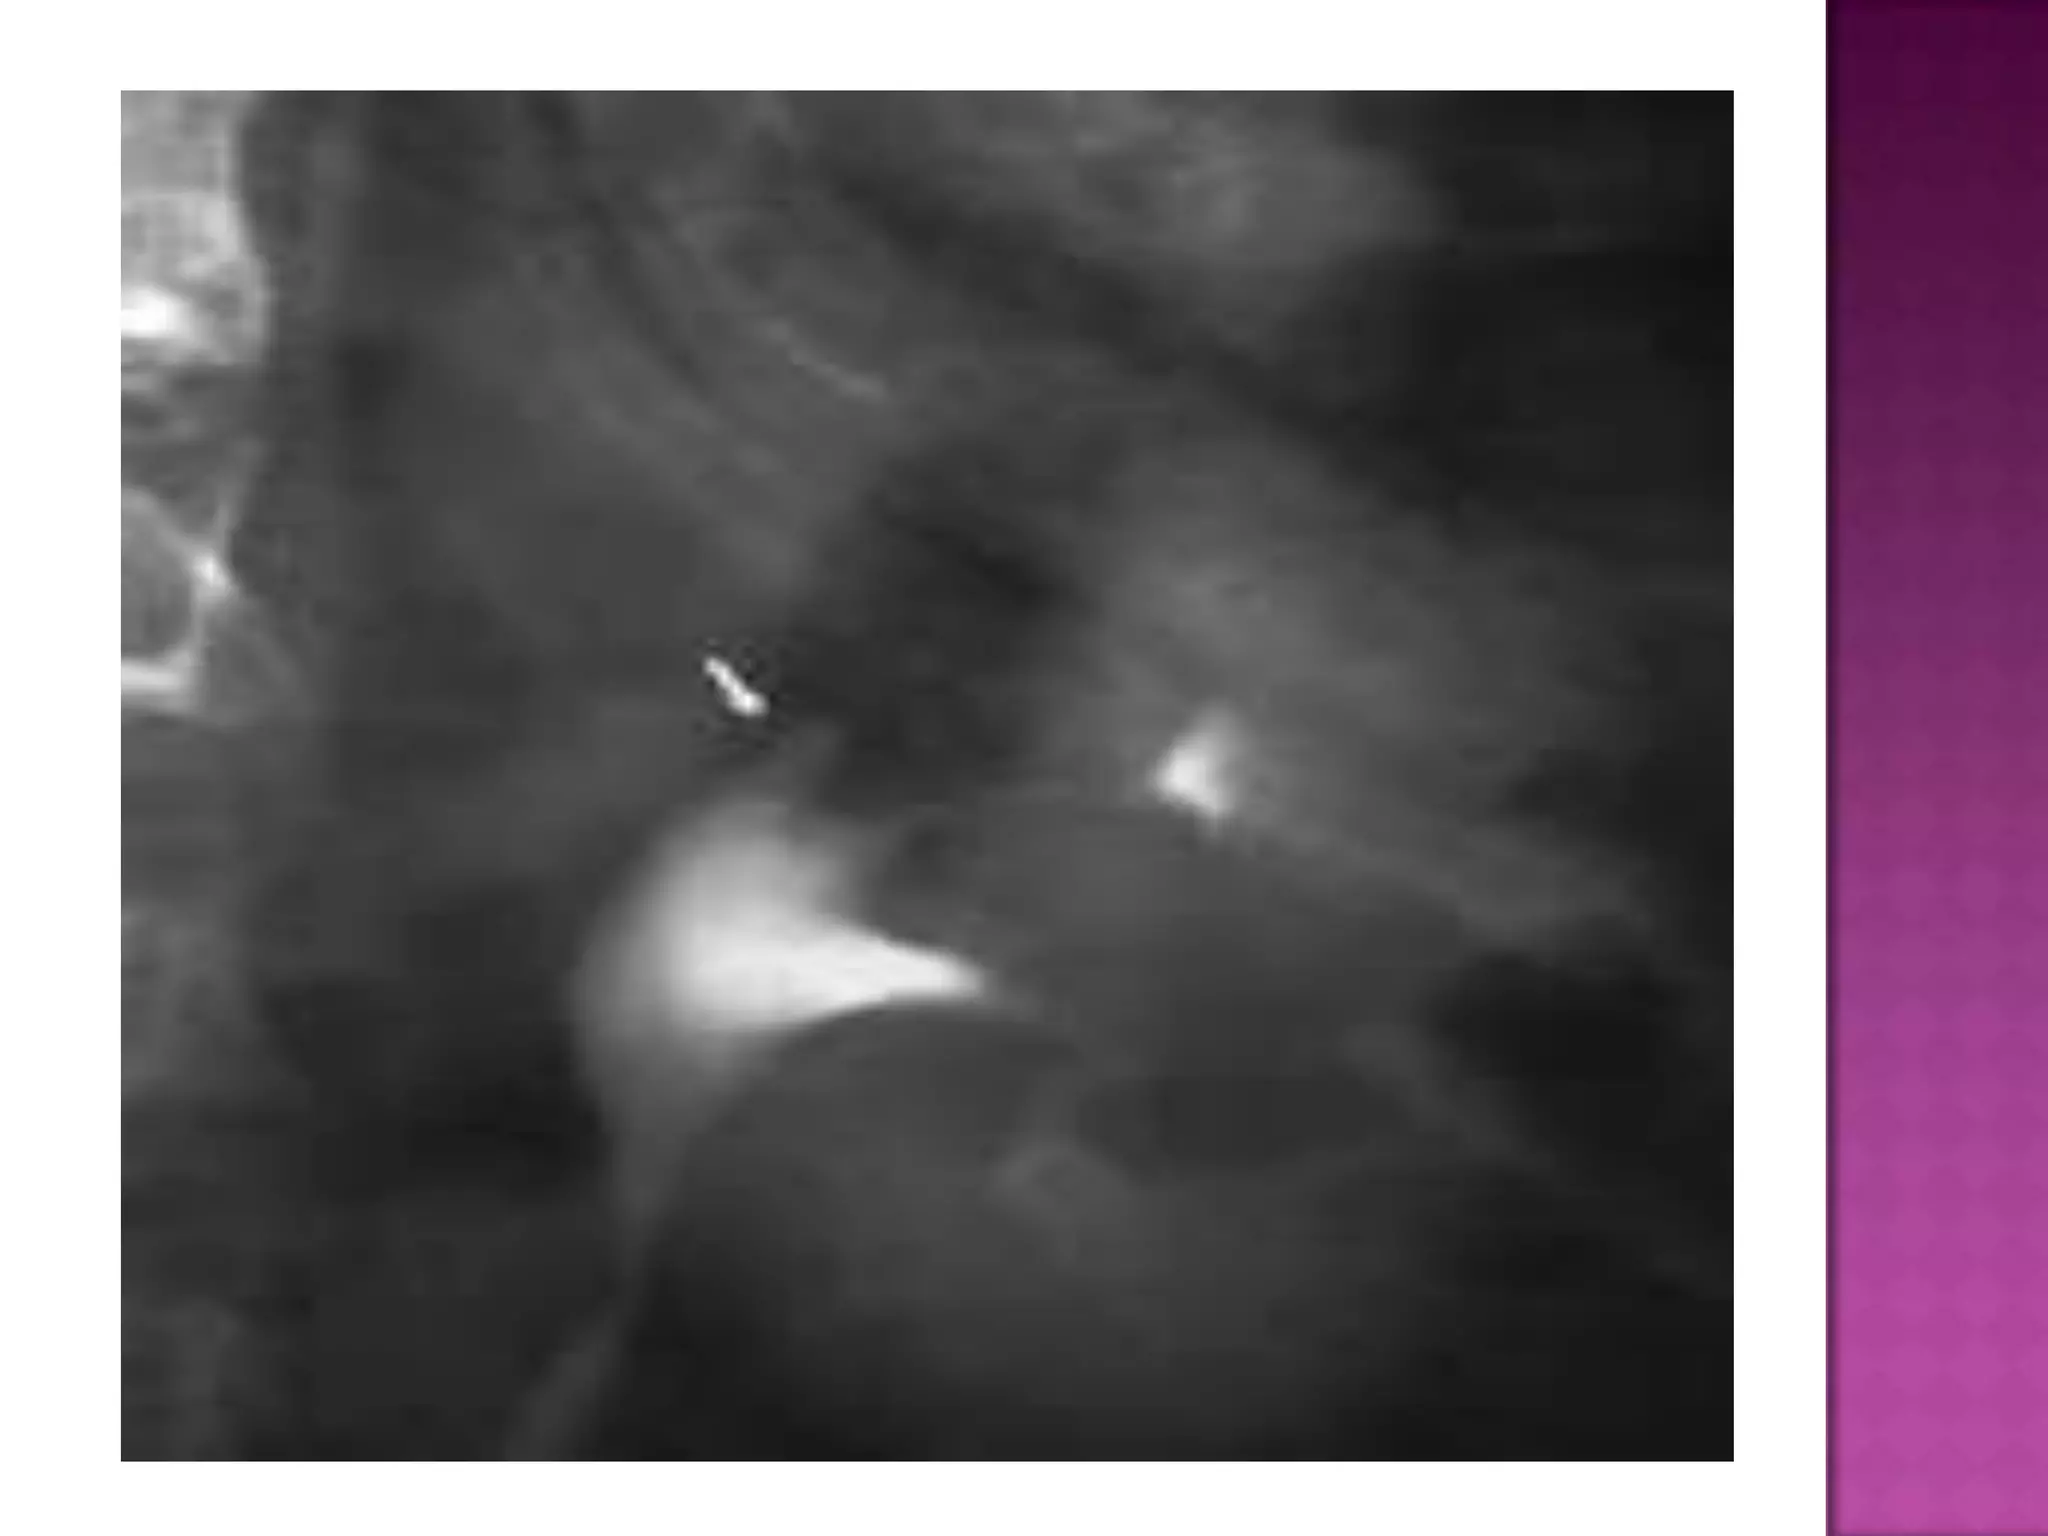

Papillary

necrosis.

Excavation

extending from

the caliceal

fornices (arrows)

produces the

lobster claw

deformity in

another patient.

Papillary necrosis. Excavation extending from the caliceal fornices(arrows) produces the lobster claw deformity in another patient.